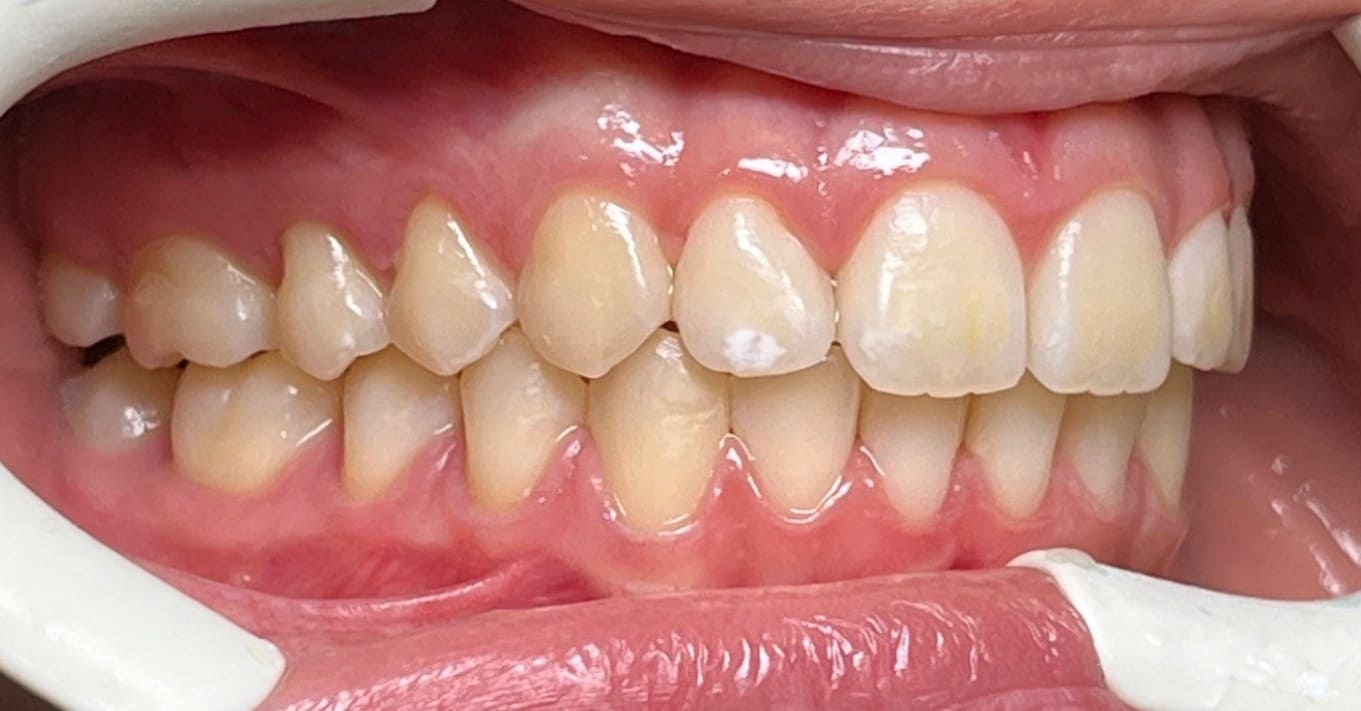

Initial

Final